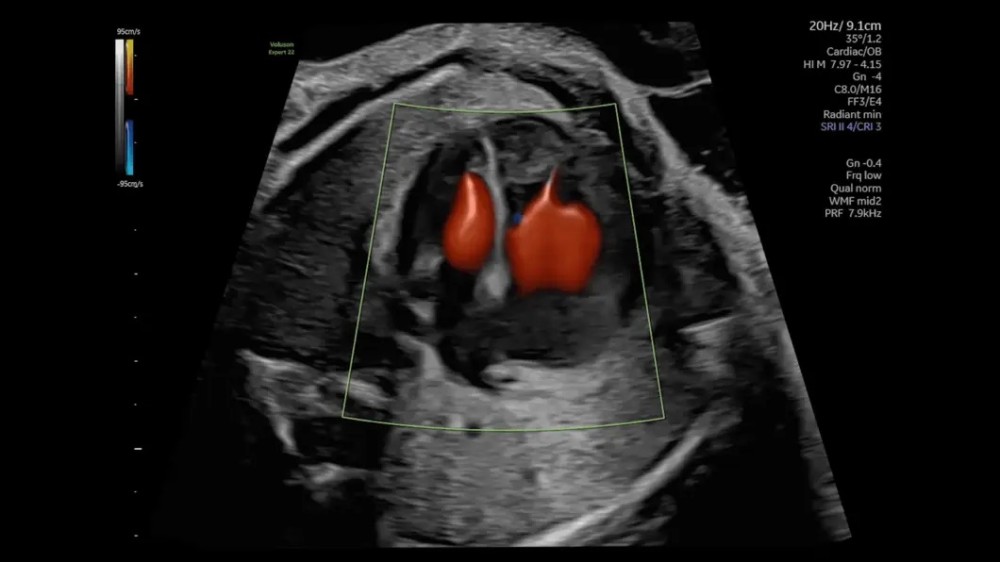

• Voluson Expert 22 real vaxtda yüksək məkan həssaslığına malik görüntülərin əldə olunmasını təmin edən avansert 4D volumetrik görüntüləmə texnologiyasından istifadə edir və bu, klinik diaqnostikanın dəqiqliyini əhəmiyyətli dərəcədə artırır.

• 3D/4D volumetrik görüntüləmə

• HDlive Studio+ (avansert render texnologiyası)